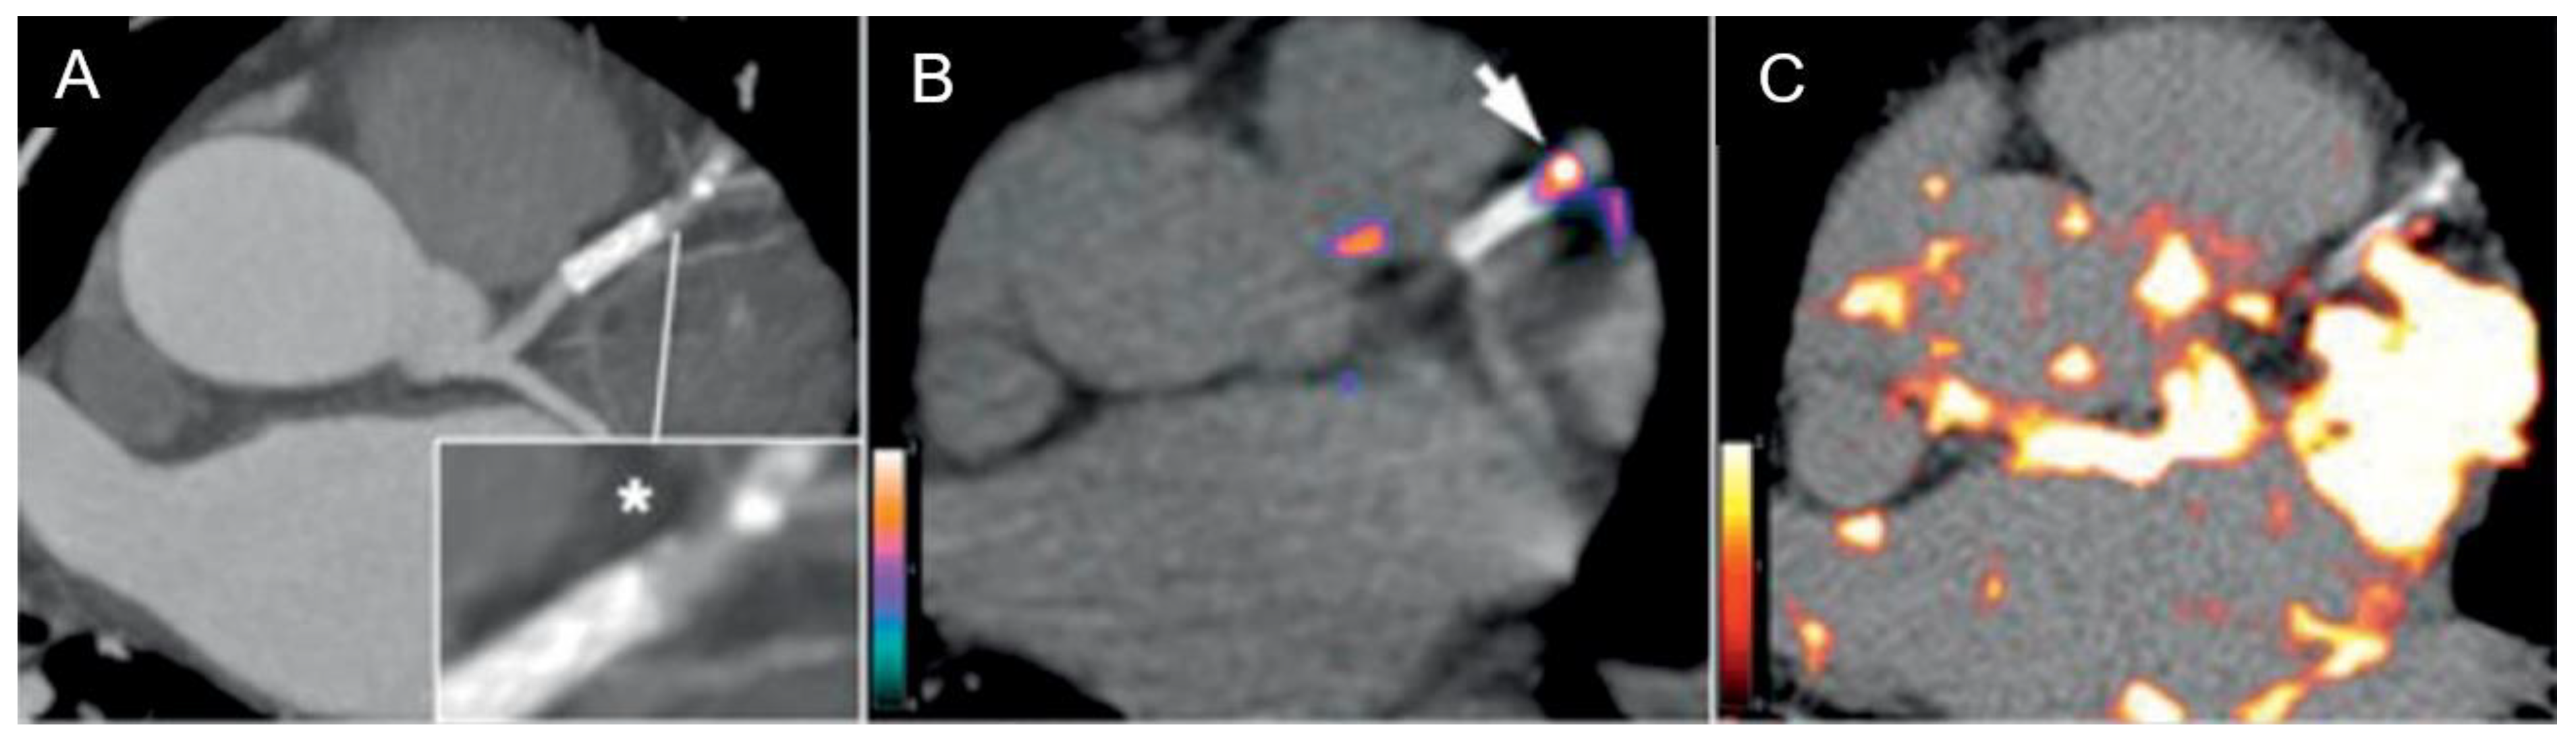

1.5. Micro-Calcifications

2. Systematic Review of 18F NaF PET in Vulnerable Plaque

2.2. Results